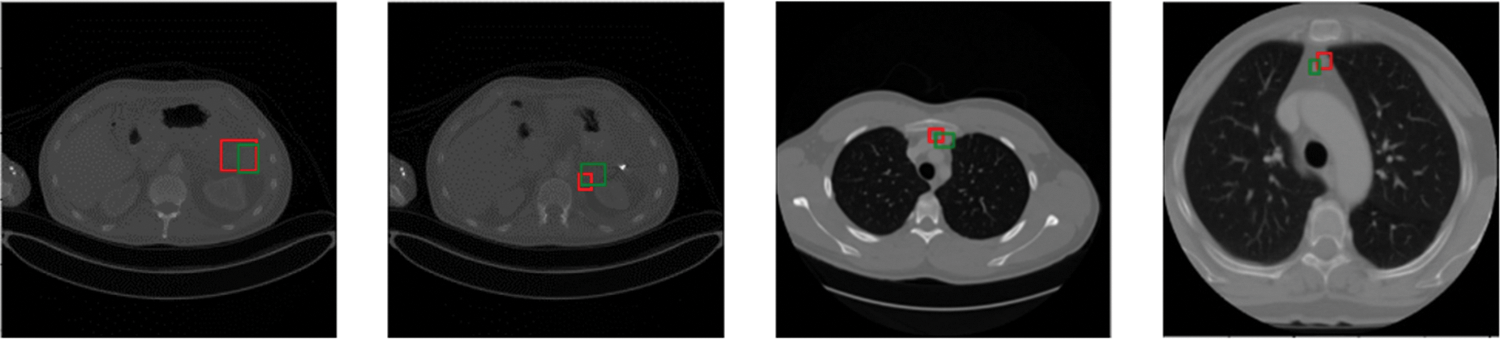

Predicted bounding boxes generated from several compared models are illustrated in Fig. 5. Our model shows superior capability to predict both the lesion location and size when compared with other methods. It is evident that the proposed method enhances the performance in detecting very small-sized or larger lesions. However, the insufficient training data for certain organ lesions resulted in inadequate generalization for the detection of these lesions as can be seen in Fig. 6.

Figure 6: Visualization of inaccurate lesion detection results. Green and red boxes correspond to ground-truths in the test set and predicted true positives